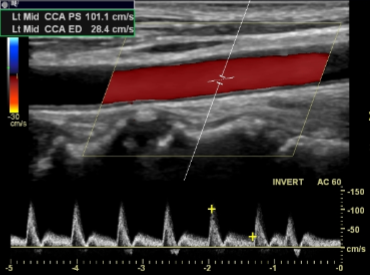

Is this image showing flow towards or away from the transducer?

Towards